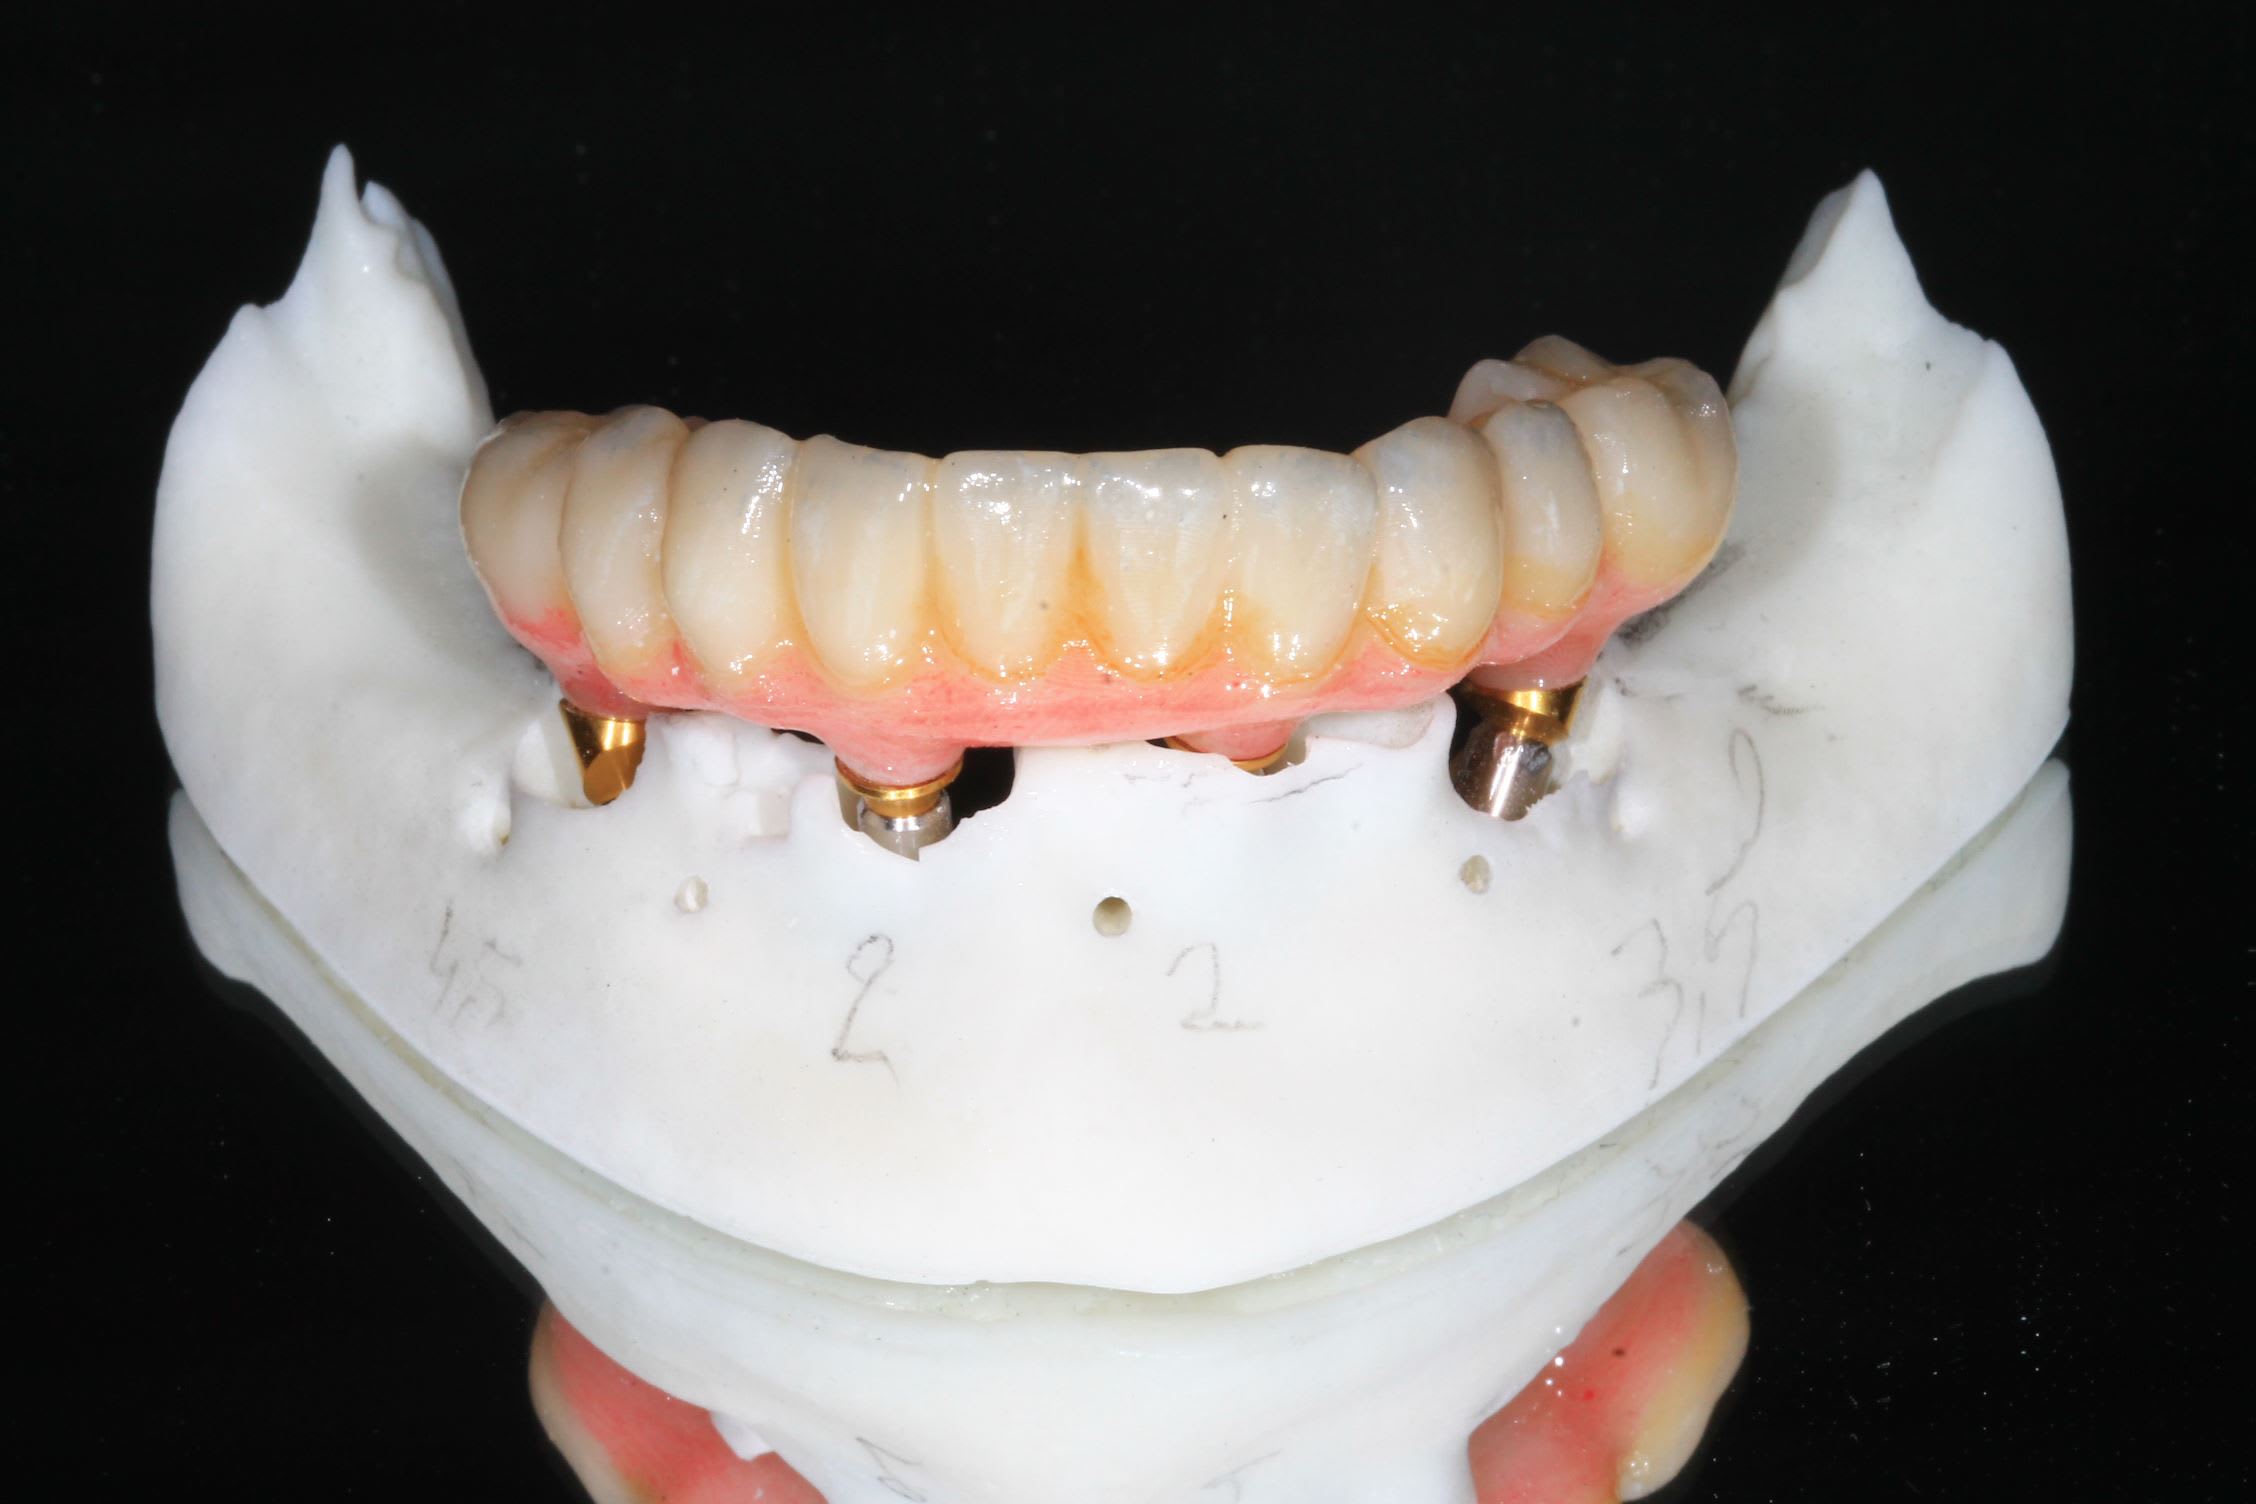

Scan et matching des scanbody dans Médit design. ( j'ai fait une video , mais pas eu le temps de la mettre en ligne, si cela intéresse )

Retour meshmixer et finition de la modélisation du bridge.

Impression sur phrozen mini 4 k avec résine Flexera et maquillage.

Tres important pour la mise en charge instantanée : la precision : bien indexer les implants sur le guide en cas de piliers angulés.

Bridge imprimé au cab , résine flexera .

Vis rosenscrew.